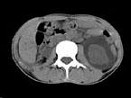

- 多项选择题女,32岁, 左腰部胀痛不适1年余,10年前因右输尿管结石、右肾重度积水行右肾切除术, CT检查如图所示,下列说法正确的是 ( )

A、平扫左肾周可见不规则的环形低密度影

B、增强扫描,肾皮质明显强化而周围的低密度影无强化

C、增强扫描肾实质期,肾实质强化而周围的低密度影无强化

D、增强扫描延迟期,肾实质强化减退而其周围则呈高密度影,对比明显

E、考虑为左侧尿外渗